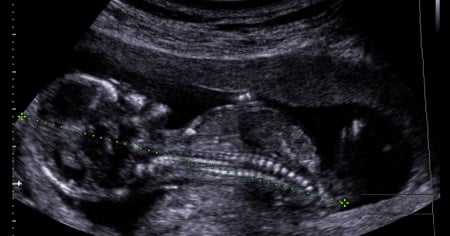

«Qualunque cosa fosse accaduta avremmo dovuto lottare per nostro figlio», in questa consapevolezza, dolorosa ed amorevole allo stesso tempo, si concentra tutta la storia di una giovanissima mamma paraguaiana che, alla dodicesima settimana di gestazione, ha scoperto che suo figlio sarebbe, quasi sicuramente, nato morto. Alla base di questa certezza c'era la diagnosi di idrope fetale, una malattia che colpisce il feto con accumuli di liquido nei tessuti sottocutanei o nelle cavità sierose. La grave condizione creata da questo disturbo rappresenta una sentenza alla quale non ci si può appellare, si può solo aspettare gli esiti del suo decorso che può sfociare in una rara remissione spontanea prima del parto o nella nella morte intrauterina o subito dopo la nascita del bambino. Il piccolo paraguaiano, Joshua, è morto il giorno dopo il parto cesareo con il quale è venuto al mondo, lasciando ai suoi genitori la pienezza di un amore incondizionato ed il ricordo di una scelta mai rimpianta, nonostante le conseguenze. L'idrope fetale, oltre ad essere estremamente pericolosa per il feto, è altrettanto rischiosa per la mamma che viene colpita dalla cosiddetta «sindrome a specchio».

Come si manifestano queste malattie? Tachicardia fetale, emorragia prenatale, eccessiva produzione di liquido amniotico, scarsi movimenti del bambino sono i sintomi solitamente associati all'idrope fetale e sono accompagnati da ipertensione, proteine nell'urina ed ingente edema sottocutaneo nella futura mamma.